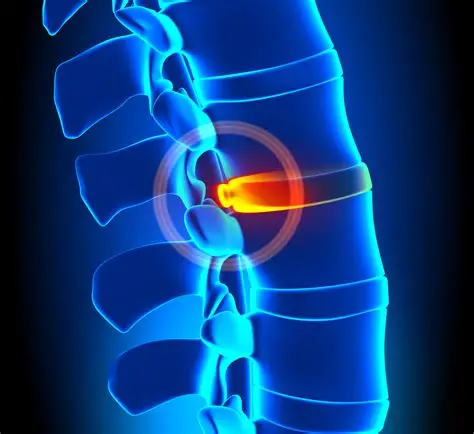

Herniated Disk Or Slipped Disc

Disc Bulge

Degenerative Disc Disease

Spondylolisthesis

Ankylosing Spondylitis

Discectomy

Laminectomy

Spinal Fusion